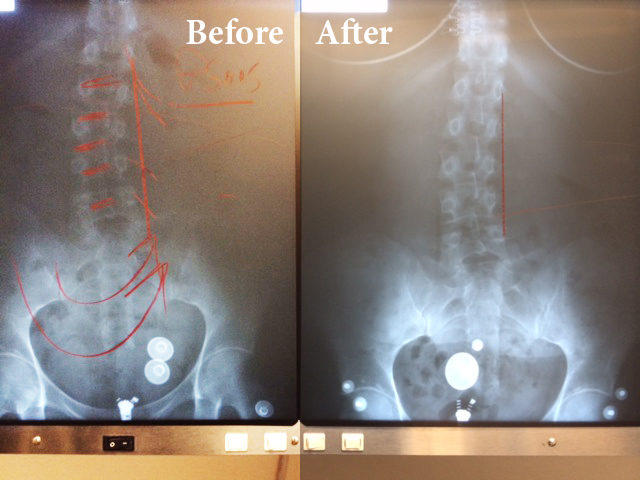

This is a 41 YOA female. The radiography on the left is the beginning of treatment. The radiography on the right is only after 8 treatments on the ATM2 Pro.